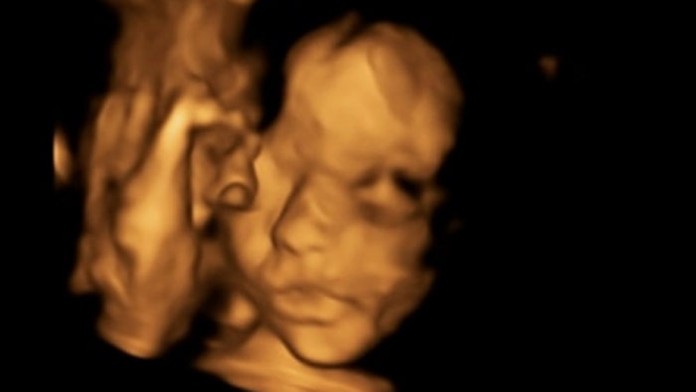

Nenarodenému dievčatku museli lekári upraviť chrbticu.

Unikátnu operáciu podstúpila tehotná Britka, ktorej bábätko malo rázštep chrbtice. Lekári dieťa vybrali z jej maternice, operovali a vrátili späť. Po štyroch týždňoch od zákroku vyzerá dievčatko, ktoré sa má narodiť v apríli, zdravo.

Na začiatku januára, kedy bola Bethan v 24. týždni tehotenstva, chirurgovia vykonali unikátnu operáciu. "Bola úspešná. Jej porucha bola len malá a ten zákrok zvládla, ani by ste neverili. Jej mozog vraj vyzeral dobre a komory sú normálne. Vyňali ju z maternice a potom ju vrátili, aby tam zostala, ako dlho bude môcť," dodala Bethan.

Počas operácie museli lekári nenarodenému dievčatku upraviť chrbticu. Matka bola plne uspaná a anestetikum slúžilo bábätku tiež ako liek proti bolesti. Procedúra podľa výskumov výrazne zlepšuje šancu dieťaťa na to, že bude normálne chodiť a pohybovať sa, oveľa viac než operácie vykonávané po narodení.

Podľa posledných správ to vyzerá, že Bethanino bábätko sa vyvíja tak, ako má. Hlavička už má normálny tvar, dievčatko rastie a gynekológ vraj ani nevidí, kde mala na chrbtici vadu.